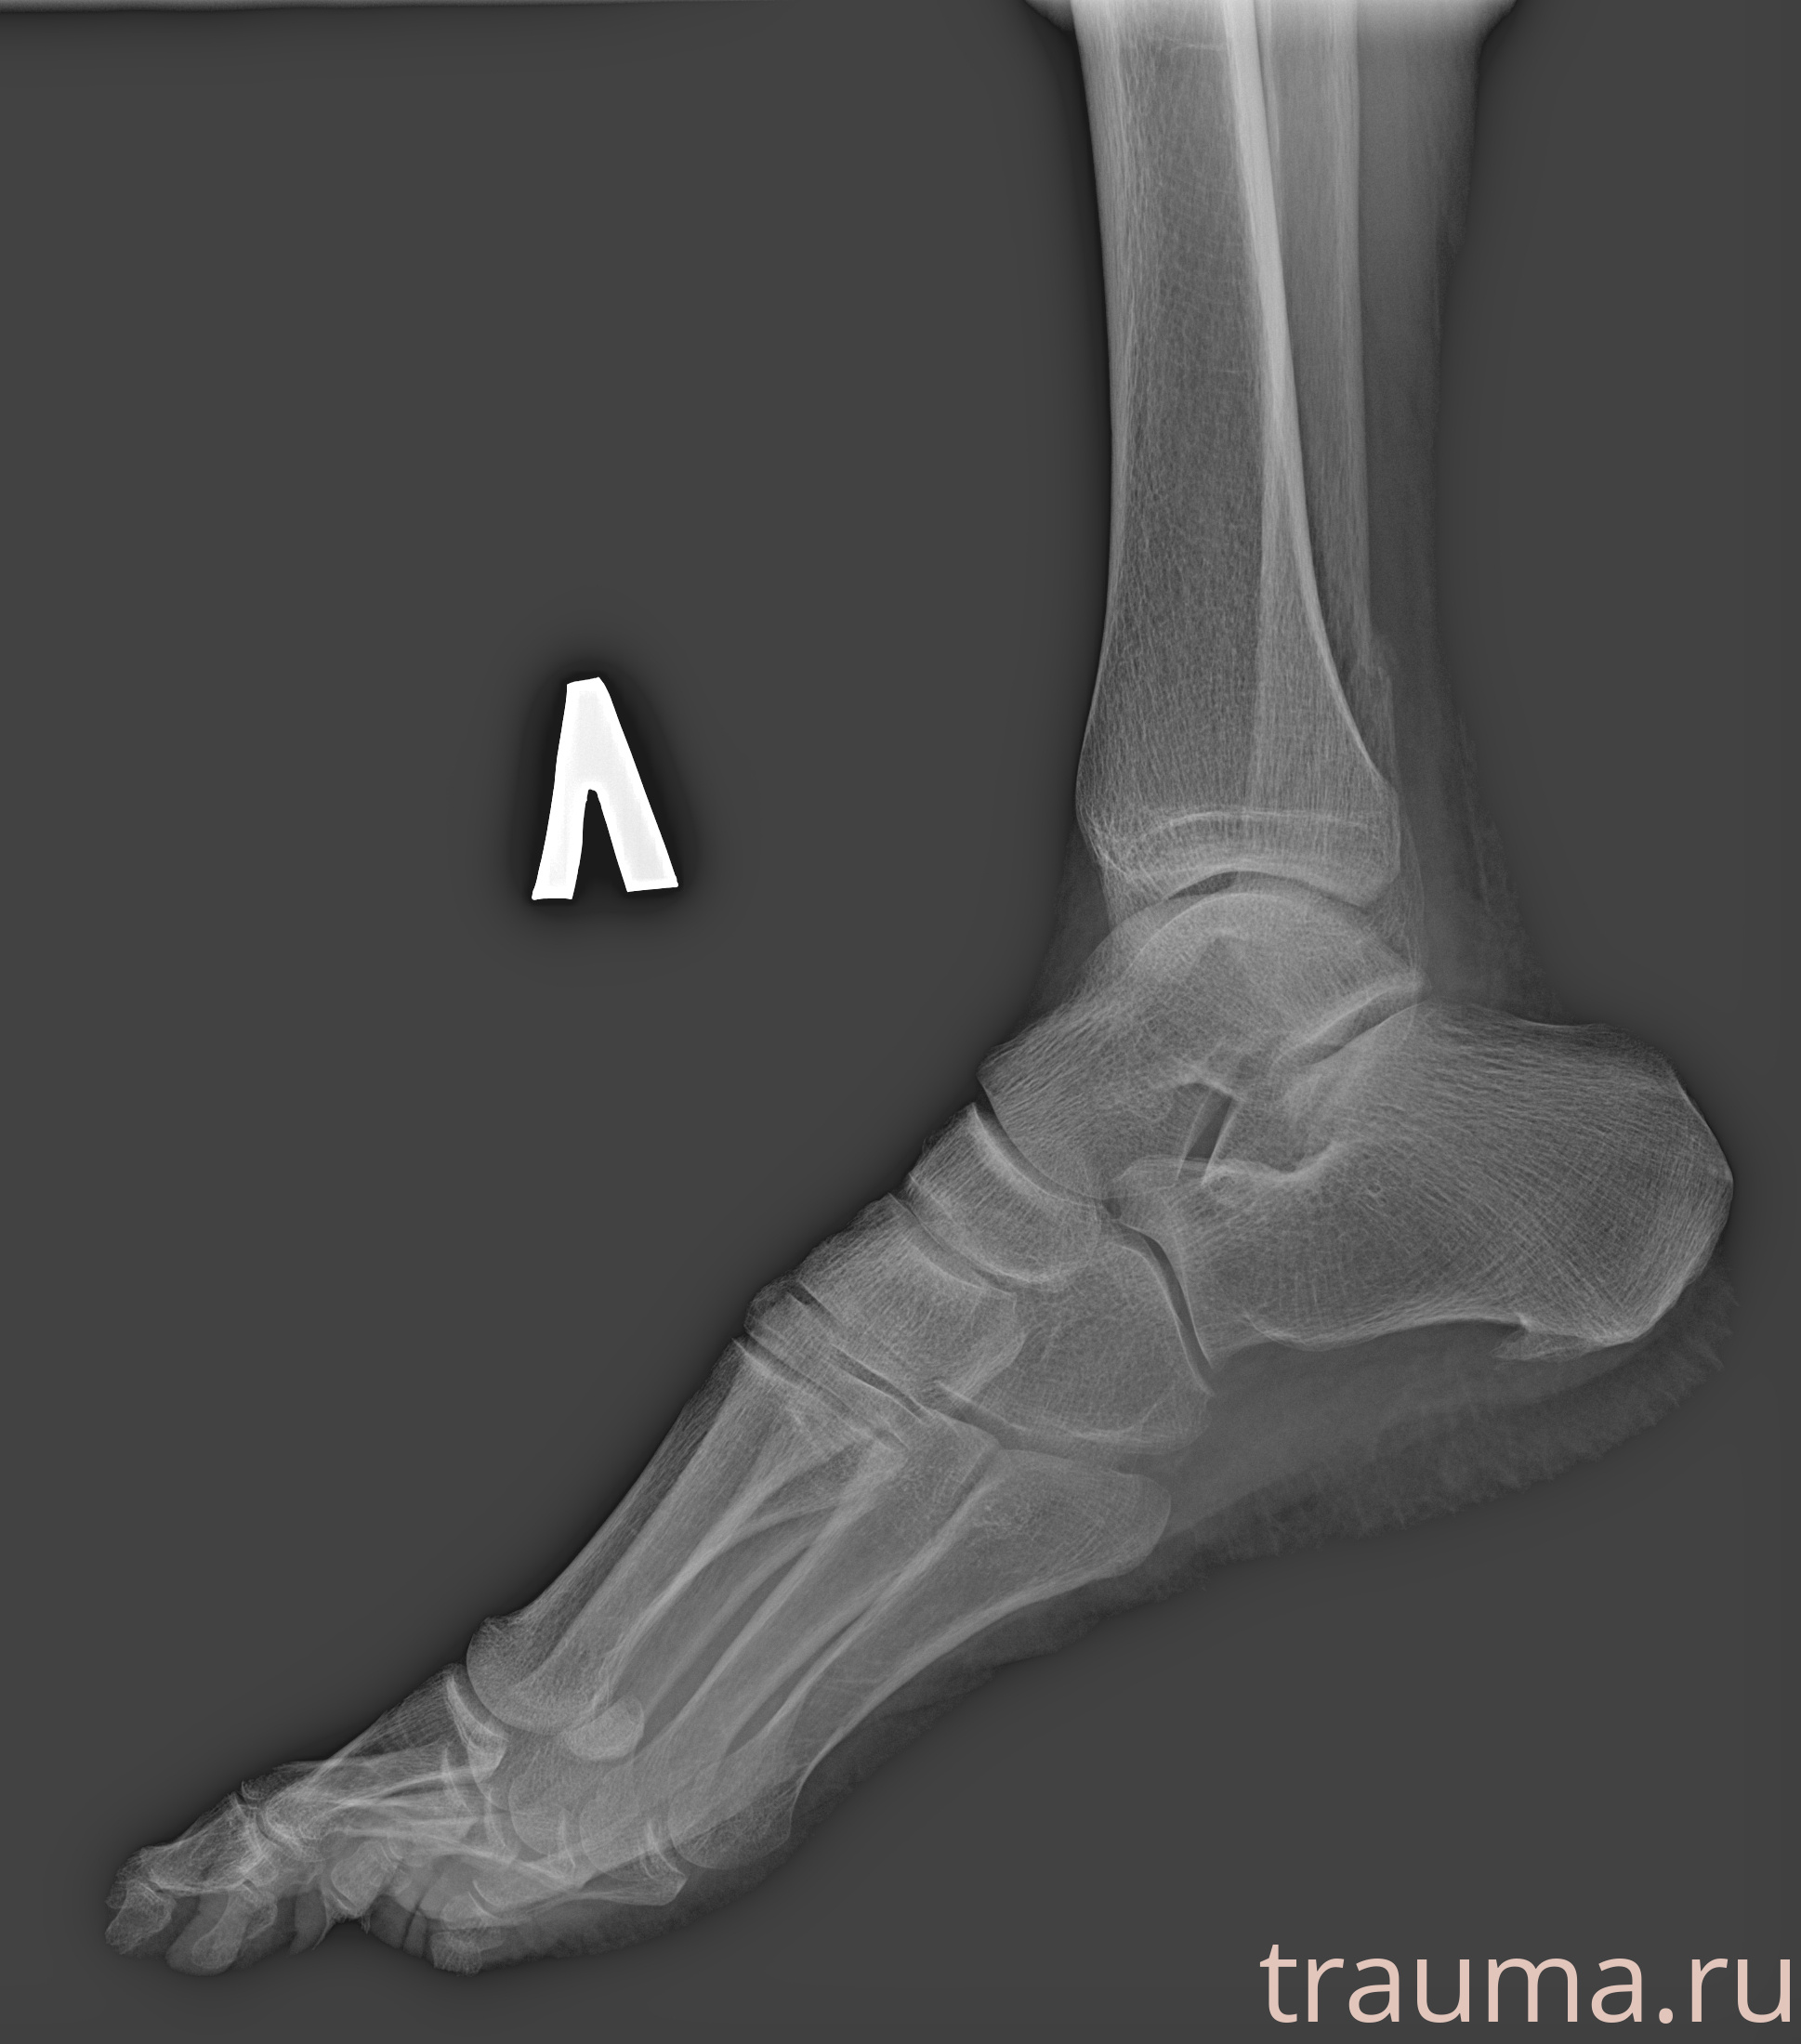

Рентгенограммы

Рентген на дому: по вашему адресу приезжает врач-рентгенолог, травматолог-ортопед с мобильным рентгеновским аппаратом, проводит диагностику травмы или заболевания, делает необходимые рентгенограммы, дает рекомендации по дальнейшему лечению. Получить качественные снимки в домашних условиях возможно благодаря уникальной методике, разработанной МосРентген Центром для института  Склифосовского